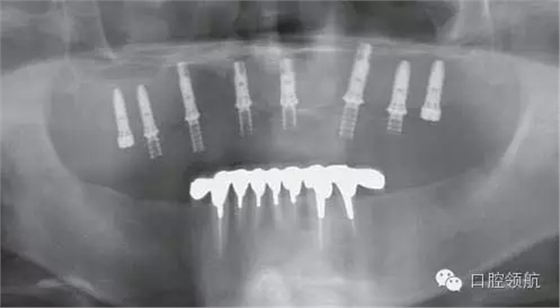

X線影像也未見異常(圖2)。

圖2 X線影像未見異常。